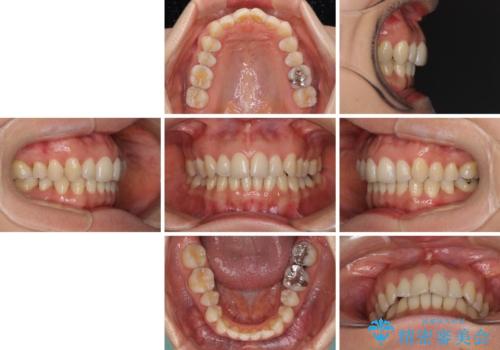

矯正治療の後戻り インビザライン・ライトによる矯正治療

- 矯正治療の後戻りを気にして来院された患者様です。

後戻りは軽微であったので、インビザライン・ライトにより矯正治療を行うこととしました。